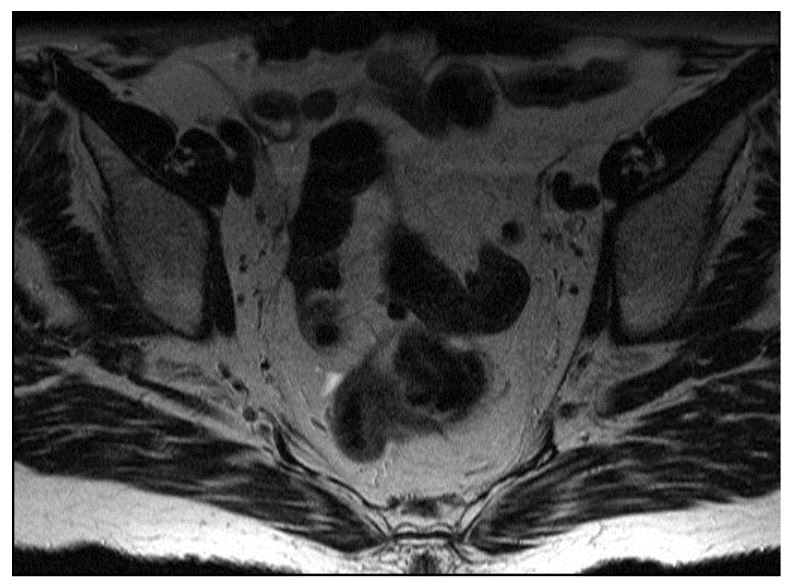

Figure 2. Extraperitoneal Tumor MRI

Note the anterior mesorectum and mesorectal fascia.